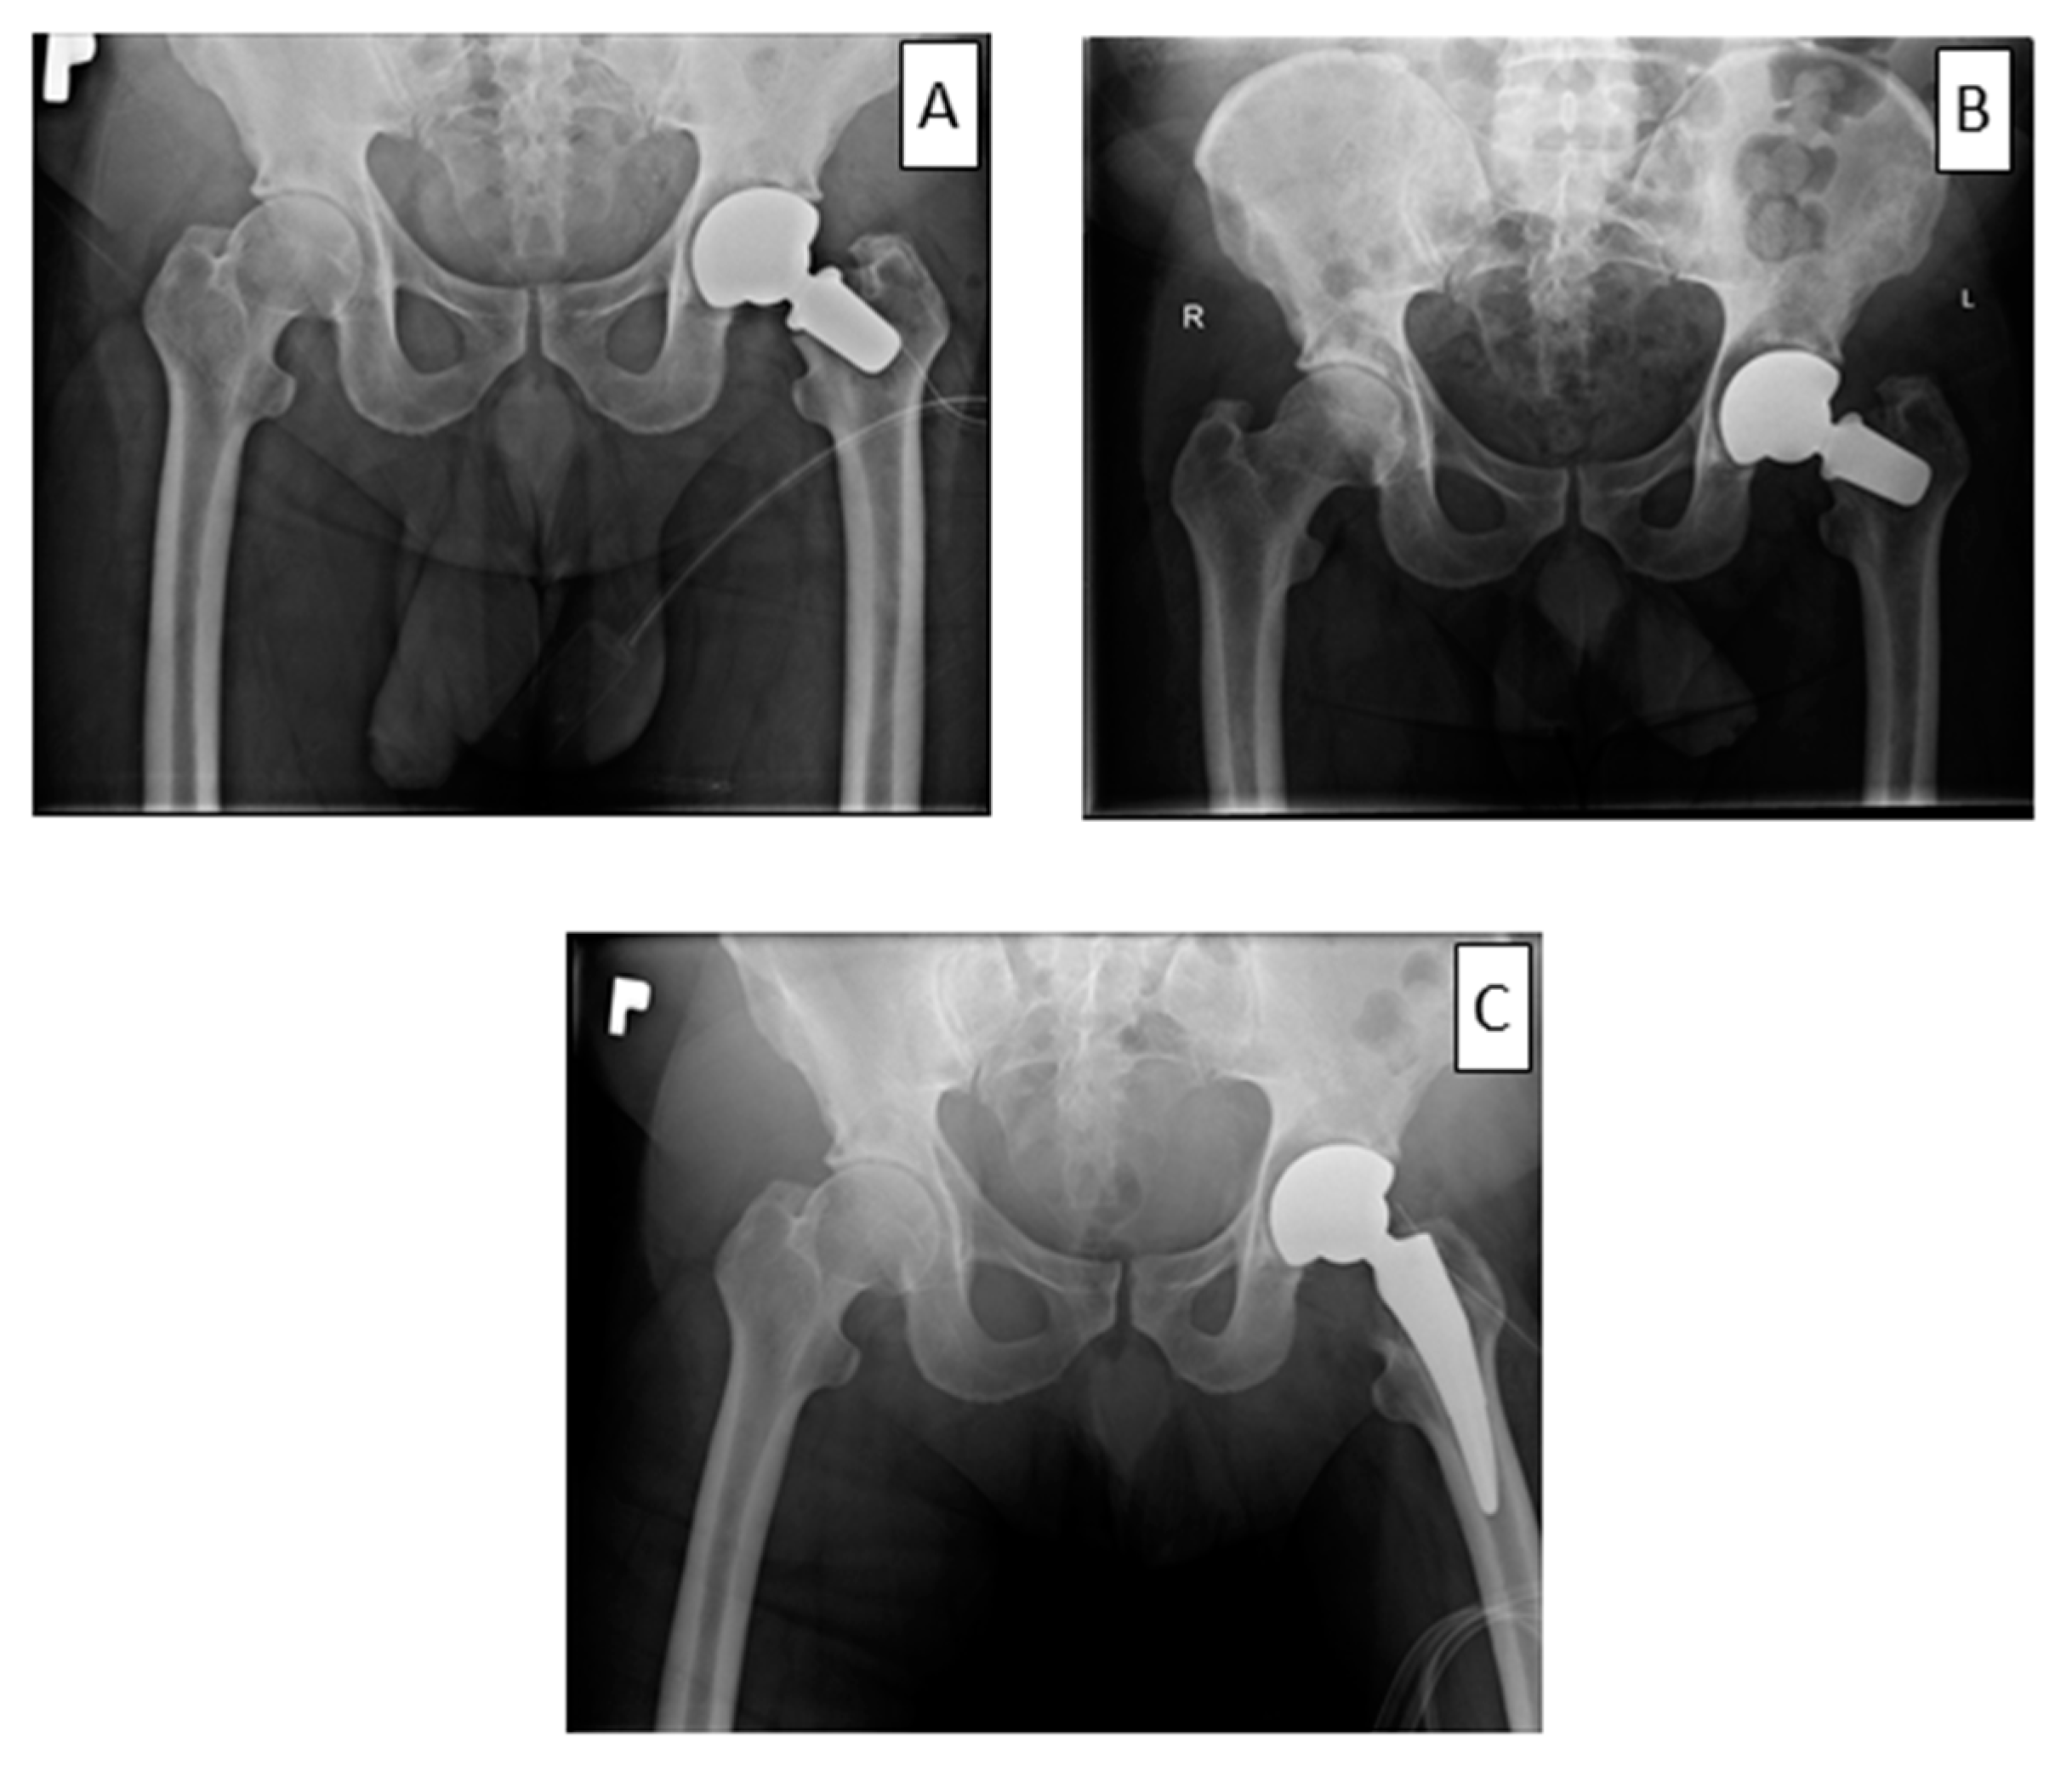

Figure 4. The case of early loosening from the short-stem group. X-ray taken after implantation (A), loosening 4 weeks after implantation (B) and after revision surgery (C).

Hip biomechanics after THA is usually affected. Implant survival is dependable on centre of the rotation, frictions and cup positioning. All these factors can lead to shortening of the implant survival [21]. Interesting experiences arose from three revisions performed on patients with a loosened femoral neck prosthesis implant shortly after the primary surgery. In all three cases, the implant was converted to an implant with a longer but conventional stem. The operations were problem-free and lasted for a relatively short time, as for a revision procedure (average 44 min). The operations required cutting the femoral neck and implementing a previously selected standard stem, which did not lead to any major technical problems. Oversized rasp, cementation, and augmentation with bone grafts were avoided. Blood loss was minimal, and none of the patients required a blood transfusion after surgery (Figure 4). Further work addressing the revision of standard and short mandrels is required to confirm these observations. In the opinion of the operator, it was easier to convert to a standard stem than to a revision implant. The decision regarding the choice of a short-stem prosthesis in younger people seems to be reasonable, mainly in the context of revision.